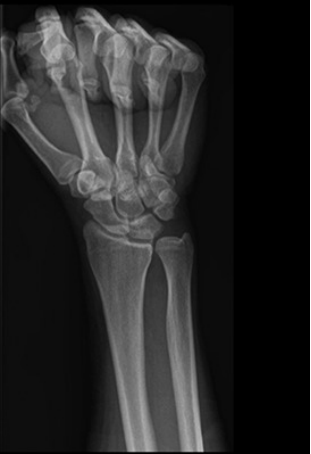

获取腕关节正位、侧位及旋前握拳位X线片,以评估尺骨变异及腕骨软骨软化(图1)。

图1 一名37岁特发性尺骨撞击综合征男性患者的术前旋前握拳位X线片显示,尺骨存在正向变异,且月骨尺侧可见囊性病变。